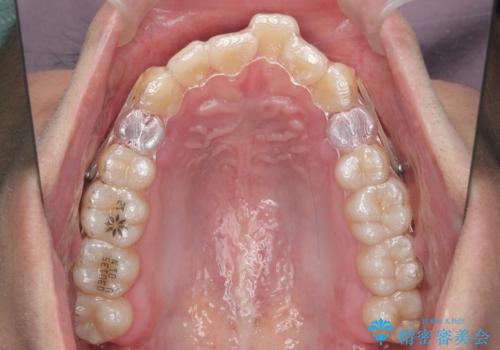

出っ歯の治療 インビザラインで抜歯矯正 親知らずを使用した矯正

- 出っ歯を主訴に来院。

上の小臼歯を2本抜歯しています。

そのかわり、上の親知らずを生かしており、歯の本数は減っていません。

矯正用ミニスクリューを使用しています(インプラント矯正)。

奥歯の歯ならびのずれが大きく、親知らずを抜いてすべて後ろに下げるか、手前の歯を抜いて前歯を下げるかの2択でした。